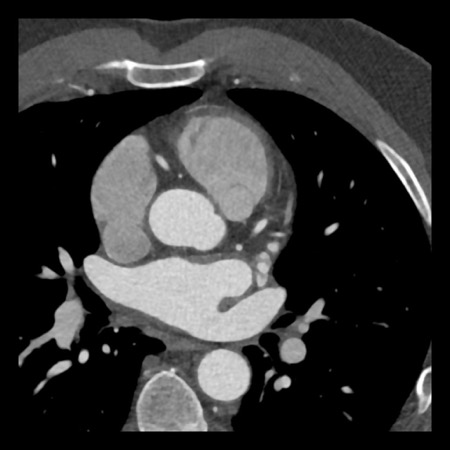

case 1 – CAD-RADS 2/P1

First, scroll through the scan.

Not all images are included. Some images without any abnormalities are skipped

from the series.

How would you describe the findings on the coronary CTA?

The findings are:

- Agatston score of

this patient was 14 (P1). Please, also note the calcification of the aortic valve. - Some partially

calcified and calcified plaques are present in the LAD with mild stenosis

(25-49%). - Calcified-plaque in

the LCX causing minimal stenosis (<25%). - Non-calcified

plaque in the distal RCA causing minimal stenosis (<25%). - This patient classifies

as CAD-RADS 2/P1, which means no further workup is needed.